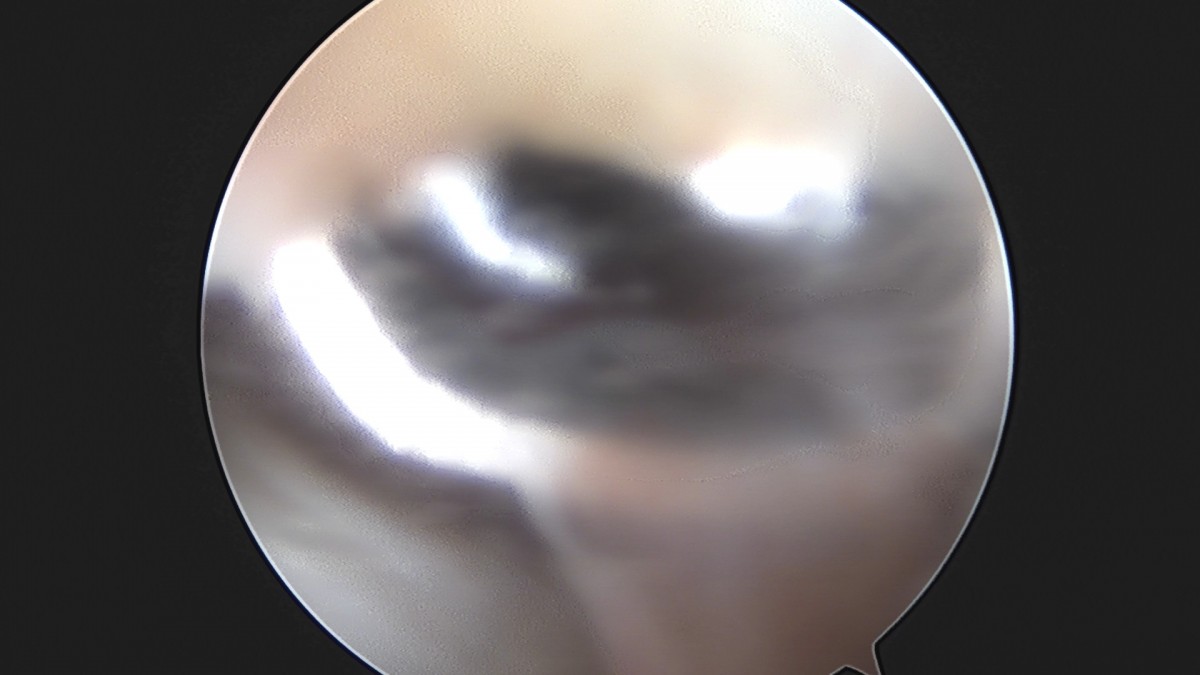

이재상원장님 무릎 반월상 연골판 절제술 장영O 환자

작성자 최고관리자 댓글 0건 조회 369회 작성일 25-09-16 16:02

dae765e4d9ac96aee867c9d6292d8784_1758006134_3414.jpg